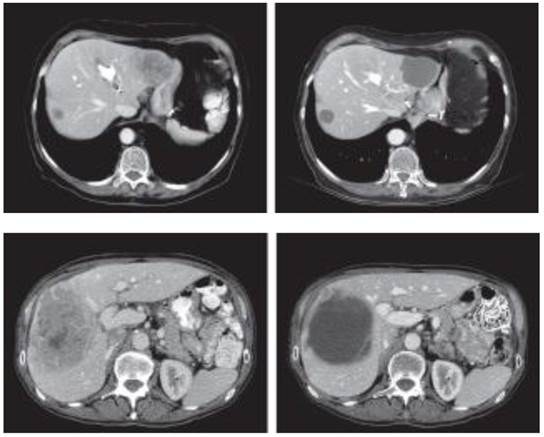

Yet, imaging also plays a role in the assessment of tumor response as well. Evaluating for any changes in number and size of the primary or metastatic lesions is a fairly standard practice. However, as technology progresses and imaging modalities become much more sensitive, size alone may not be the only indicator of response on imaging. Chun et al. observed that in patients treated with bevacizumab for metastatic colon cancer, the most relevant aspect of tumor response is a modification of the computed tomography morphology, involving a transformation of the metastases from heterogeneous lesions with thick, irregular borders into bland, homogeneously hypodense masses with a sharp, non-enhancing interface between the tumor and adjacent liver parenchyma (Figure 3).36 Morphologic criteria correlated strongly with the percentage of residual tumor cells and also with pathologic response whereas RECIST did not. Furthermore, patients with optimal morphologic response had median overall survival of 31 months (95% CI, 26.8-35.2 months) compared with 19 months (95% CI, 14.6-23.4 months) with incomplete or no morphologic response (P=0.009).36 These results highlight the importance of radiological response in addition to baseline clinical factors in determining patient outcomes.

Figure 3

Transformation of the metastases from heterogeneous lesions with thick, irregular borders into bland, homogeneously hypodense masses with a sharp, non-enhancing interface between the tumor and adjacent liver parenchyma. Courtesy of Chun et al. 36